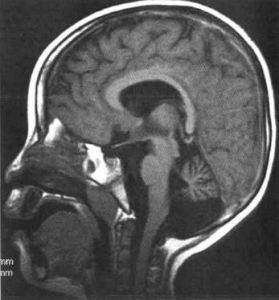

多數患有嬰兒神經軸索營養不良/非典型神經軸索營養不良而導致小腦萎縮的病人都可以在相對較早的年齡通過MRI被評估出來。與此同時,若出現腦部含鐵量高或視覺萎縮的症狀,即可確診,通過基因測試可以確認診斷結果。